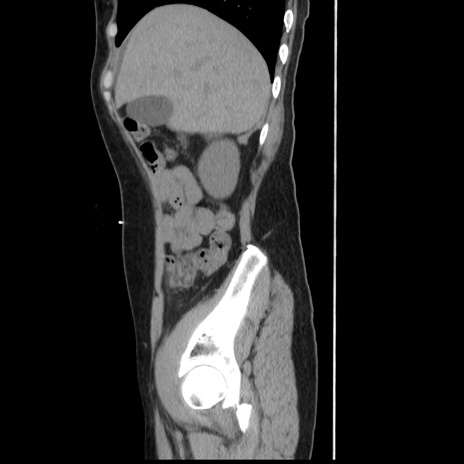

症例10(矢状断像)

【症例】 50歳代女性

【主訴】 腹痛

【現病歴】前日生レバーを食べた。今朝に排便あり。 昼前に突然発症の腹痛を生じ、当院救急外来を受診した。

【既往歴】 子宮筋腫にてで子宮全摘後

【身体所見】 意識清明、腹部:平坦、軟、下腹部やや左を中心に圧痛・反跳痛あり、筋性防御あり

【データ】WBC 7800、CRP 0.07